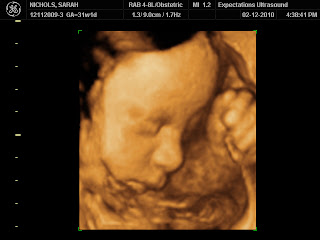

31 Week 3D/4D Utrasound

On Friday, February 12, we went for our final 3D/4D ultrasound.  We were told she would be a little "chunkier" than last time and that we would not be able to get as many full body pictures.  She was definitely bigger than 10 weeks ago!  We have been so lucky with all of our previous ultrasounds because she cooperated so well and were were always able to see what wanted needed to see (gender . . .) and get great pictures of her cute little face.  Well, this one was a little different!  She either had both feet, or both hands, in front of her face for the entire 30 minutes.  We tried switching me onto both sides, standing up, jumping, laying down . . . nope, she was not about to put those hands down!  So, here are a few pictures where you can actually see her face!  She is even smiling in one of them!  Soooo cute!  I can't wait to hold her in just a few weeks (well, as compared to 36 weeks when I found out - it does seem like "just a few week!")!